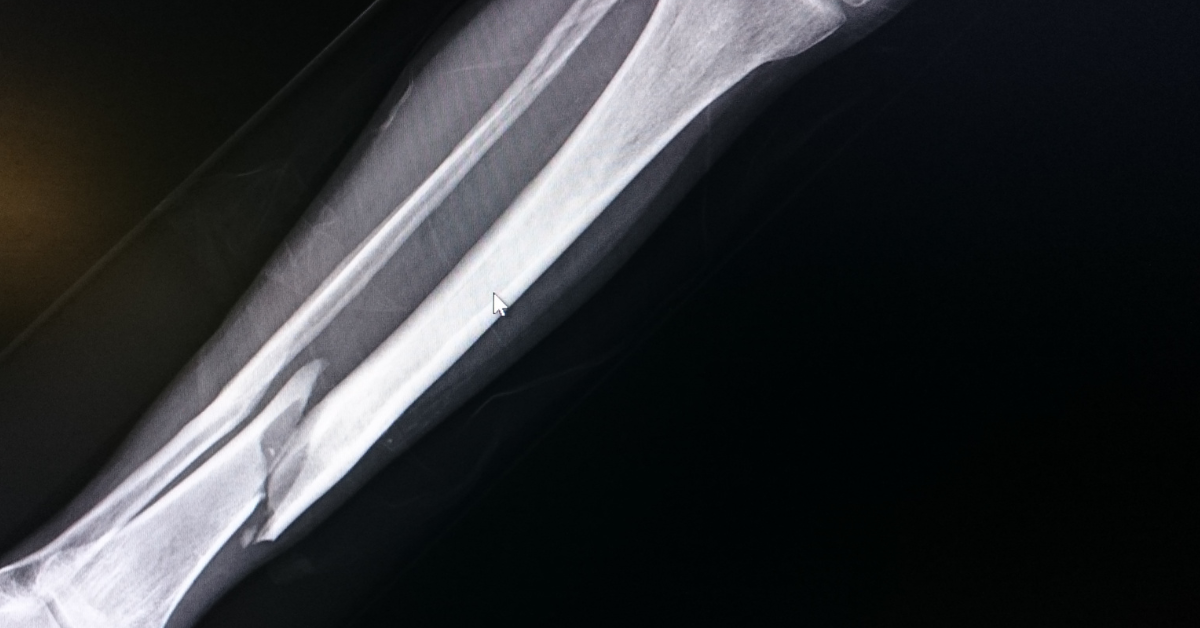

In most cases, a broken bone can heal smoothly after proper medical treatment. However, in some patients, the fracture does not heal in the expected period despite treatment, and we give this type of fracture another name called a non-union fracture.

Generally, if the fracture does not heal in 6-9 months, it can be considered a non-union fracture. Studies have shown that about 5-10% of fractures may result in non-union, and the tibia, humerus, talus, and fifth metatarsal bone are the most commonly affected.